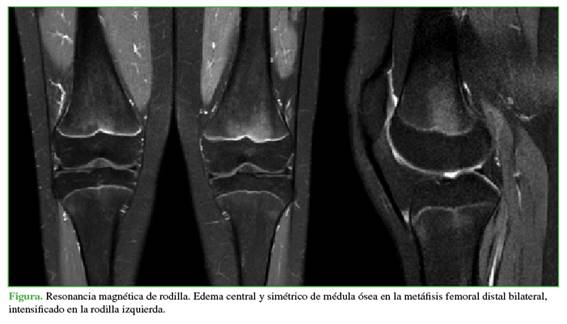

A los tres meses, acudió a la consulta de control, luego de ser evaluada por los médicos del Servicio de Reumatología, sin un diagnóstico específico. Continuaba con dolor intenso en la rodilla, y entregó una nueva RM realizada en forma particular, en la cual se visualizó claramente una lesión FOPE en el fémur distal, sin otros hallazgos patológicos (Figura). Por lo tanto, se diagnosticó lesión FOPE en la tibia proximal y el fémur distal de la rodilla izquierda. Se les explicó a la paciente y a la madre la baja prevalencia de este cuadro y se le ofreció un manejo con terapia física y analgésicos.

Áreas de edema en la región metafisaria y epifisaria de la fisis

Edema simétrico

Hipointensas en la secuencia T1, hiperintensas en la secuencia T2

Extensión variable

Localizada en la porción central de la fisis/ligeramente excéntrica

Fisis estrecha ligeramente abierta en el área del edema